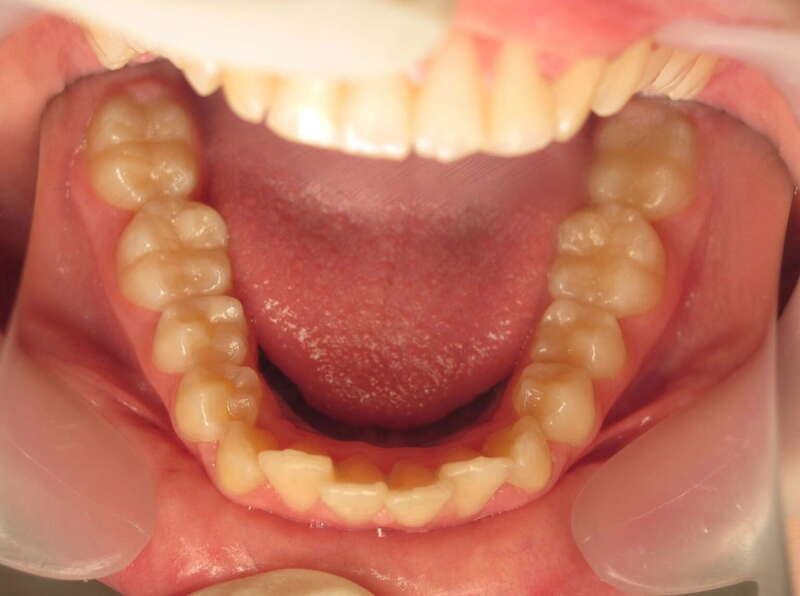

Cas n°9 traité par multi-attaches - adolescent

Ce cas d'adolescent illustre une stratégie de développement d'arcade réussie. Le patient présentait un encombrement massif et des inversions d'articulé rendant l'occlusion instable.

Le traitement a été réalisé avec des multibagues autoligaturantes, choisies pour leur capacité à générer des forces légères et continues, idéales pour l'expansion transversale. Cette approche a permis de corriger l'encombrement et les inversions d'articulé sans extractions dentaires, en remodelant simplement la forme des arcades.

Résultats clés :

• Transformation d'arcade : Passage d'une arcade étroite et encombrée à une arcade large et fonctionnelle.

• Occlusion optimale : Rétablissement d'un engrènement sain, protégeant les dents contre les usures anormales.

• Esthétique naturelle : Le sourire est élargi, harmonieux et parfaitement intégré au profil du patient.

C'est une démonstration de l'efficacité biologique de l'orthodontie moderne, qui privilégie la conservation dentaire et le respect des structures osseuses.